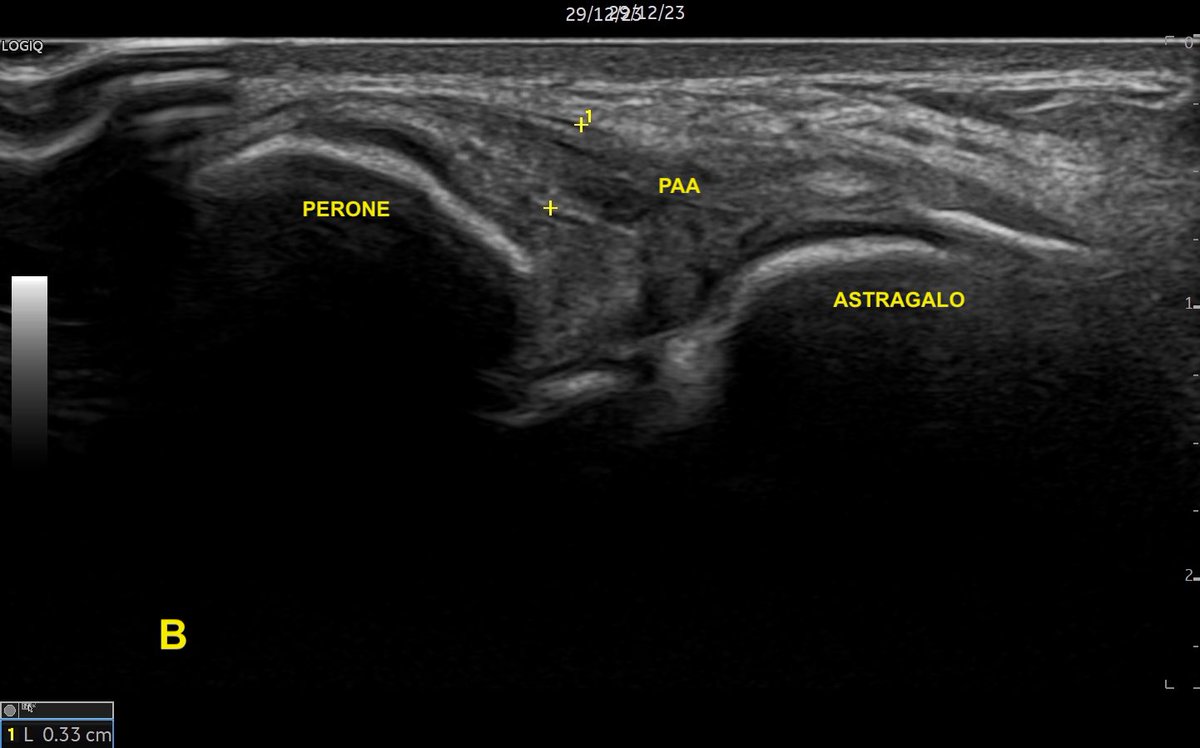

Tobillo inestable: #ecografia del fascículo peroneo astragalino anterior roto parcialmente. Imagen A, ligamento roto en su mayor parte (grosor 1.4mm). Imagen B del mismo ligamento: área conservada con un grosor de 3.3mm. Conclusión: siempre escanear toda la amplitud del ligamento